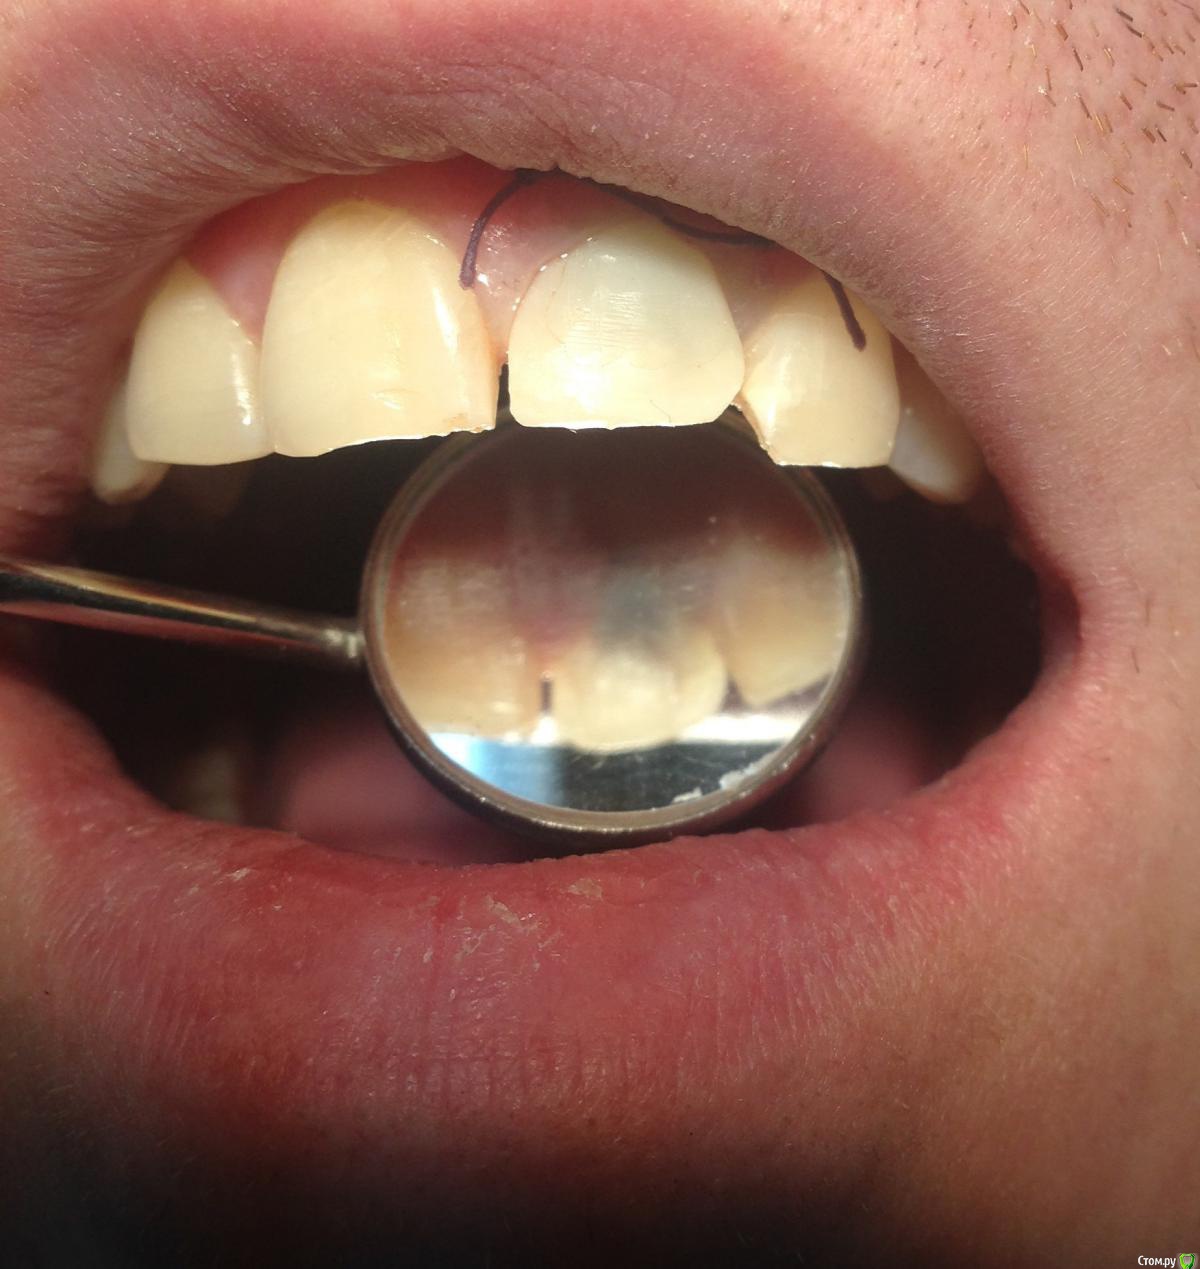

Популярный пост Фарид Расулыч Опубликовано 20 декабря, 2014 Популярный пост Поделиться Опубликовано 20 декабря, 2014 (изменено) Пациент обратился с проблемой, на производстве выбило зуб полетевшей в лицо "фиговиной". При осмотре коронка сломана глубоко под десну. Принято решение удалять и имплантировать с одномоментным временным протезированием. Работа производилась в конце смены, поэтому фоткать было особо некогда. Но кое что заснял. Удалил корень, имплантировал (заглубил имплант), подшил маленькую сст-шку (пожалел что маленькую, надо было жиренй), снял слепок (десневой маски под рукой не было, модель вся из гипса), сделал на обычном абатменте времяшку (были под рукой только обычные абатменеты, на них и воспроизводил сию лепнину), прикрутил. Самовыводы: не торопиться, сст жирней, времяшки не на обычных абатментах, ибо жалки да и пробивает метал. Через какое то время наверно переделаю времянку и зениты подровняю, но пациента все устраивает. Что скажете вы?? Изменено 20 декабря, 2014 пользователем Фарид Расулыч 23 Ссылка на комментарий

Чертков Александр Опубликовано 20 декабря, 2014 Поделиться Опубликовано 20 декабря, 2014 Отлично! Только "канаты" не айс... Ссылка на комментарий